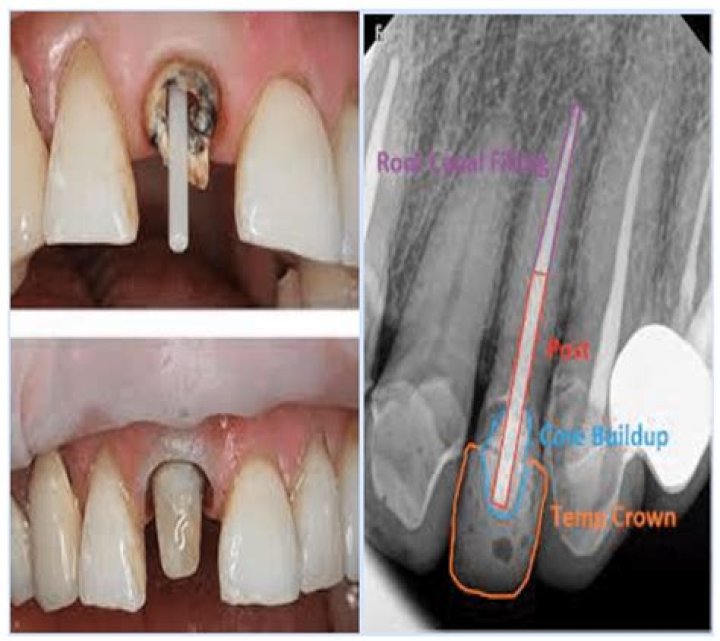

A core buildup is a restorative dental procedure that involves replacing missing tooth structure with special filling material so that it can successfully support a dental crown. The filling is usually prepared in the mouth using tooth-colored composites.

When there is a large amount of missing tooth we usually rebuild it with a filling material which is called Core Buildup. The purpose of the core buildup is to replace missing tooth structure, create optimal geometry for the crown restoration and protect integrity of the tooth.

Is a post and core necessary?

The post and core are essential for reinforcing the tooth and creating a firm bond for a dental crown that lasts.